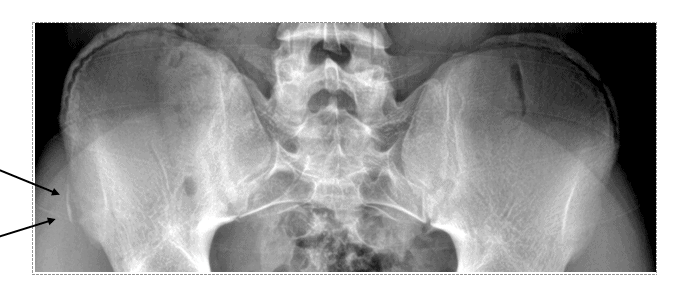

This patient was diagnosed with an avulsion fracture of the anterior superior iliac spine (ASIS), an injury that occurs most often in young athletes. It results from sudden, forceful contraction of sartorius and tensor fascia lata.

- ASIS fractures occur as acute-onset injuries (though chronic stress fractures can be a predisposing factor)

- These injuries result from sudden, vigorous contractions (or repetitive contraction) of the sartorius and tensor fasciae latae muscles